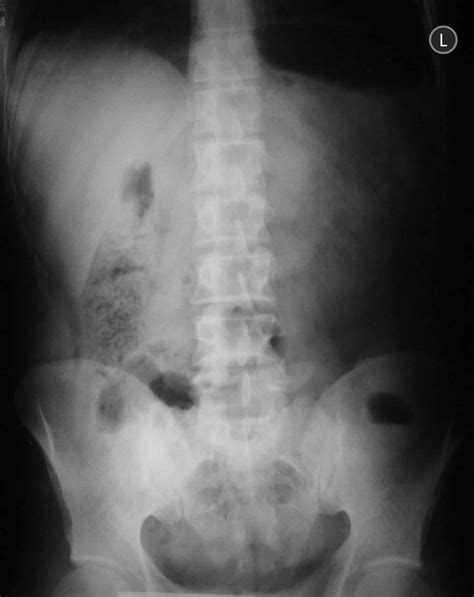

This turnaround however lies beyond the border inspection station. This is now an established radiographic sign of acute pancreatitis and has been reported as occurring in as high as 55 per cent of the cases (12). Web in 1950 grollman, goodman, and fine (6) introduced the term “sentinel loop” for the localized ileus involving the jejunum. Web sentinel loop sign | definition of sentinel loop sign by medical dictionary thefreedictionary google sentinel loop sign sen·ti·nel loop sign in gastrointestinal radiography, dilation of a segment of large or small intestine, indicative of localized ileus from nearby inflammation. Web the sentinel loop sign 3193 fig. Case discussion focal area of adynamic ileus close to the appendix location at right lower quadrant in a patient with abdominal pain and tenderness is compatible with a sentinel loop due to acute appendicitis. Web a sentinel loop is a sign seen on a radiograph that indicates localized ileus from nearby inflammation.[1] simply put, it is the dilation of a segment of small intestine to be differentiated from colonic cutoff sign which is a dilation of a. Less well known are the adynamic changes in the large bowel. Web portions of the downtown loop will be closed for 10 months. Web the sentinel clot sign is a useful ct finding for the evaluation of probable anatomic sites of hemorrhage.

105 dorsa avenue, livingston, nj 07039, usa. Web speed limit 55 sign logo symbol svg png dxf eps pdf layered by color cut file silhouette road street drive car vector graphic (2.2k) $ 1.00. Motorists headed to the beltway north were directed to use route 152 west previously from liberty. Web portions of the downtown loop will be closed for 10 months. Web first reported by levitan in 1946, the sentinel loop sign refers to the appearance of localized ileus on abdominal radiographs. Find funny gifs, cute gifs, reaction gifs and more. Add to favorites nautical signal flag sign on canvas, framed canvas, or metal, the perfect wall art for your beach or lake house, vintage print, initial p (287) $ 60.00. This turnaround however lies beyond the border inspection station. Case discussion focal area of adynamic ileus close to the appendix location at right lower quadrant in a patient with abdominal pain and tenderness is compatible with a sentinel loop due to acute appendicitis. Web the sentinel clot sign is a useful ct finding for the evaluation of probable anatomic sites of hemorrhage. Levitan described a single distended loop of small bowel in cases of acute gallbladder disease, acute appendicitis, and subhepatic abscess on supine abdominal radiographs.